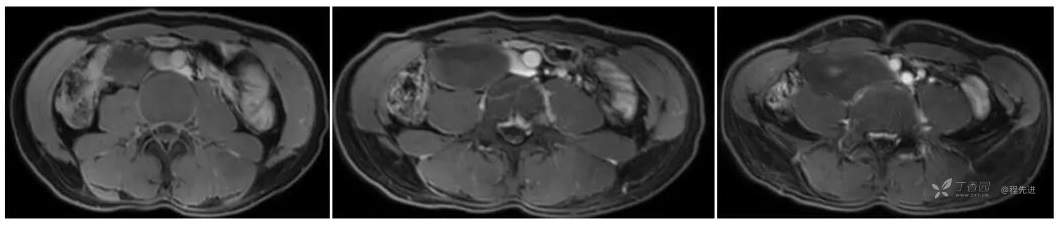

增强